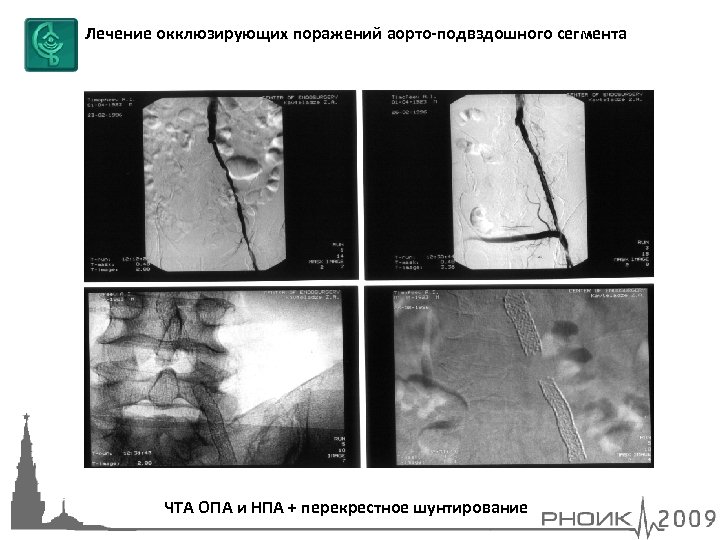

Лечение окклюзирующих поражений аорто-подвздошного сегмента ЧТА ОПА и НПА + перекрестное шунтирование